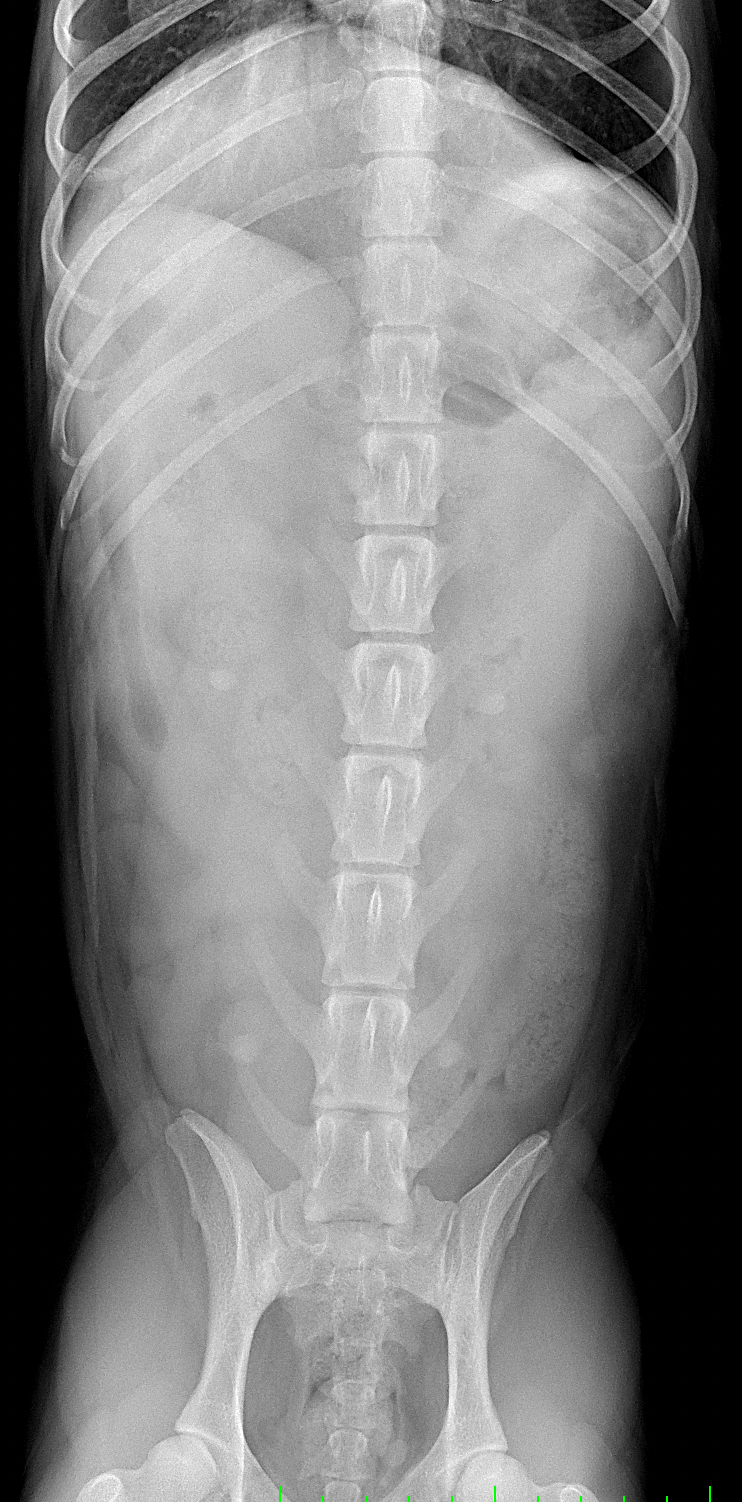

1週間前に団子を串ごと誤飲した可能性があるワンコが急にぐったりしているとのこと。すぐに地元の救急病院を受診すると異物による胃穿孔が疑われました。外科的な摘出と腹膜炎によるクリティカルケアが予想されたため紹介来院しました。開腹後、竹串による胃穿孔が確定されました。腹膜炎も同時に起こっています。穿孔創を封鎖し、腹腔洗浄とドレインの設置を行いました。幸いにも48時間後に食欲が出て退院となりました。愛犬が竹串を誤飲してしまったら、命に関わる事態に発展する可能性もあるため、早めに内視鏡による摘出をお勧めします。このような異物を発見するためにはエックス線よりも超音波検査が非常に有効です。